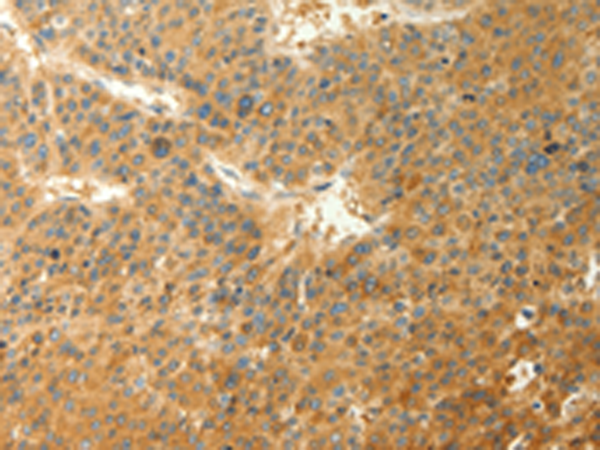

分类: 科研抗体货号: P10660别名: AMPK; AMPKa1应用: IHC反应种属: Human, Mouse, Rat

-